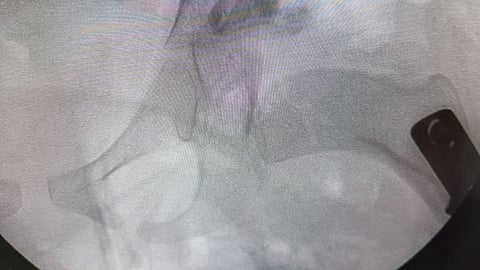

في إنجاز طبي لافت، نجح فريق طبي من قسم جراحة العظام في مستشفى المانع بالخبر، بقيادة استشاري جراحة عظام الأطفال الدكتور إبراهيم البراهيم، في إجراء عملية دقيقة لطفلة تبلغ من العمر أربع سنوات كانت تعاني من خلع ولادي مزدوج في مفصل الورك وتشوه في رأس عظمة الفخذ مع انحراف في عنق العظمة بالجهتين.

وأوضح الفريق الطبي أن هذا النوع من العمليات يُجرى عادة في عمر السنة، ما يجعل نجاحها في هذا العمر المتأخر إنجازًا طبيًا يُحسب للمستشفى وللكادر الجراحي بفضل خبرتهم وكفاءتهم العالية.

وأكدت إدارة المستشفى أن العملية تكللت بالنجاح الكامل، حيث استعادت الطفلة عافيتها بفضل التنسيق المتكامل بين أقسام جراحة العظام والتخدير والتمريض.